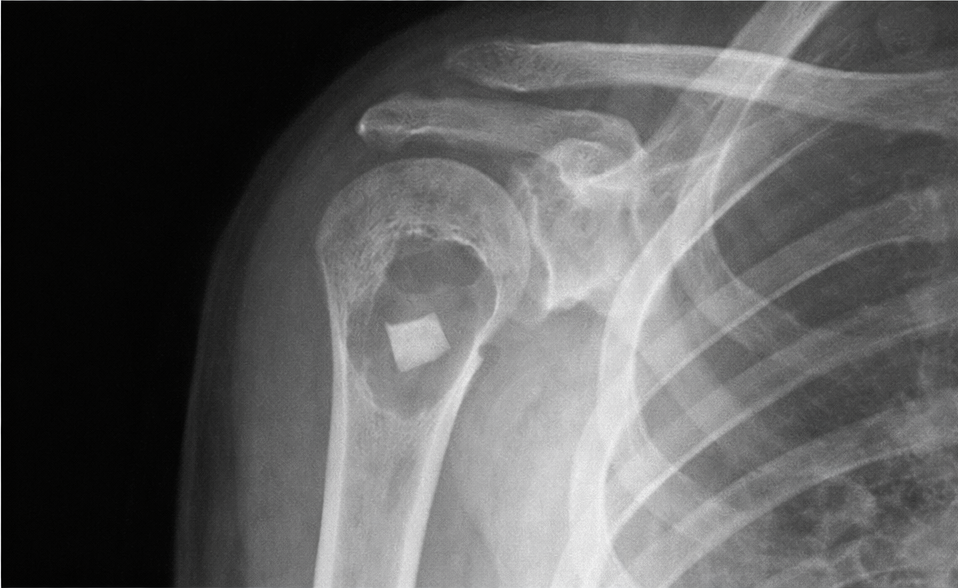

5.1 Radiografía simple (clave)

- 🔹 Lesión lítica central, bien delimitada, metafisaria (a veces diafisaria), con adelgazamiento cortical.

- 🔹 Sin reacción perióstica salvo que exista fractura.

- 🔹 Signo del “fragmento caído”: fragmento cortical dependiente dentro de una cavidad con contenido líquido (muy sugerente).

Hallazgo radiológico característico